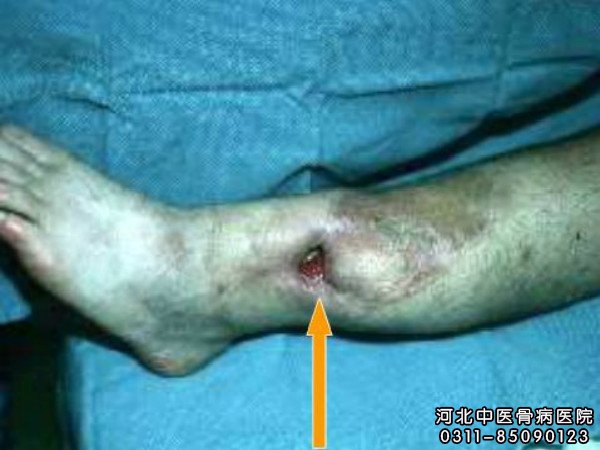

早期骨髓炎怎么办?河北中医骨病医院专家介绍:在门诊中,经常遇到有些患者觉得症状轻、也不疼,就久拖不治,结果造成严重并发症,这样是非常危险的。早期骨髓炎应该立即选择对症的治疗方式,这样患者受罪少、花钱少、效果好,尤其是有些分型的骨髓炎患者,在早期可以避免手术之苦,采用中医内服外用相结合,同样可以达到治疗的目的。

专家解释,这就是说,要早期发现、早期治疗,把疾病消灭在萌芽阶段,说明了既病防变的重要性。硬化性骨髓炎一部分是化脓性骨髓炎的延续,慢性骨髓炎又多是急性骨髓炎迁延而来。如果能将骨髓炎尽早地控制或消灭在早期,慢性骨髓炎或硬化性骨髓炎发生也就可能减少。在这方面,正确的诊断是一个重要环节。因此,在发病初期,应注意观察,结合化验、X线片等,及早作出诊断。一经确诊,就应采取积极的治疗措施,力争将其控制、消灭在初期阶段。

河北中医骨病医院骨髓炎治疗专家谢景龙主任,以其30余年的临床经验,找到骨髓炎不易治疗的机理是:骨髓炎乃余毒湿热,深居筋骨,阴血凝滞所致,据此理论拟方谢氏骨炎清系列,在中医扶正固本、清热解毒等中药内服与外治的同时,利用先进的显微外科技术,进行一次性病灶彻底清除和骨皮缺损修复。该项技术的优点是病灶清除彻底,移植的骨皮瓣血运丰富,抗感染能力强,创面修复快,一次完成手术,缩短了治疗时间,痛苦小、费用低、效果好,在经治的来自三十一个省、市、自治区两万多例骨髓炎患者,治疗率极高,对于死骨溶解变活骨达骨质复活期,大大缩短了时间,遥遥领先于同行。